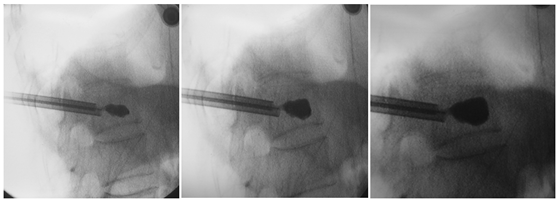

透视定位

穿刺位置的好坏,是决定手术质量的关键点。

术前透视定位伤椎

以椎弓根途径为例,皮肤进针点,为穿刺针针尖离椎弓根眼外缘1.5cm左右。

经椎弓根穿刺 ⬇

引导丝指引

取出针芯置入引导丝。

取出穿刺针外管沿引导丝放置工作通道:外鞘过椎体后缘3-5mm。

建立球囊通道

使用钻子开通道。

侧位相钻子直至椎体前中1/2交界处,正位钻头尖位于椎弓根影与棘突连线中点。

钻子必须出外鞘前端2cm,保证球囊完全进入椎体。

侧位像钻头尖在距椎体前缘2mm处停止正位显示钻头尖位于棘突边缘。